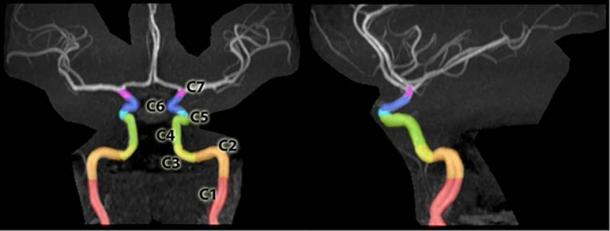

Segments of the internal carotid artery at the base of the skull that allow arteries to pass to the brain, delineated on an MRA of the head. (CC BY-SA 3.0 )